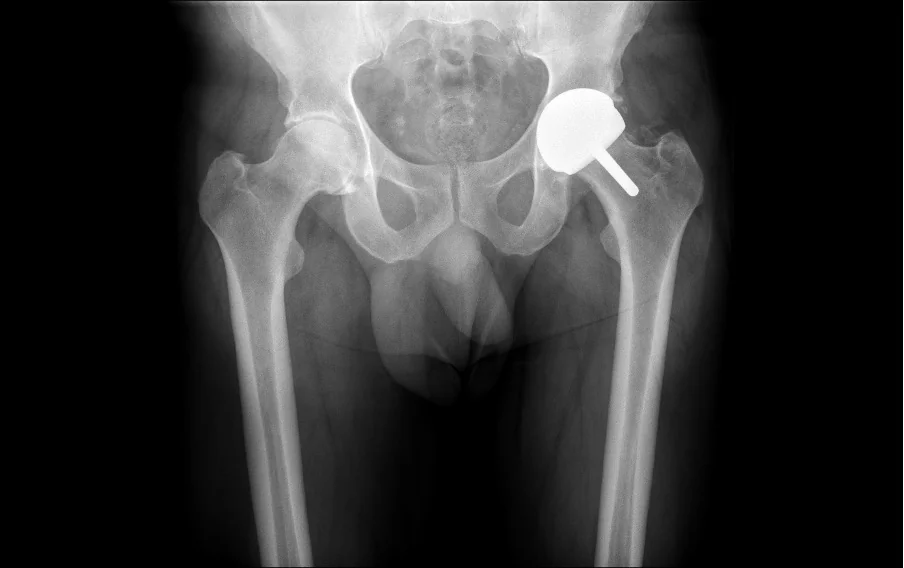

Surgical Images & X-rays

Hip resurfacing is a surgical procedure that treats hip arthritis while preserving significantly more of your natural bone than a traditional total hip replacement. Instead of removing the entire femoral head (the ball of the hip joint), it is reshaped and capped with a smooth metal or ceramic covering. The damaged hip socket is also resurfaced with a matching shell.

A proven metal-on-metal resurfacing system with excellent long-term results. Used primarily in male patients with adequate femoral head size. Well-established track record with robust clinical evidence.